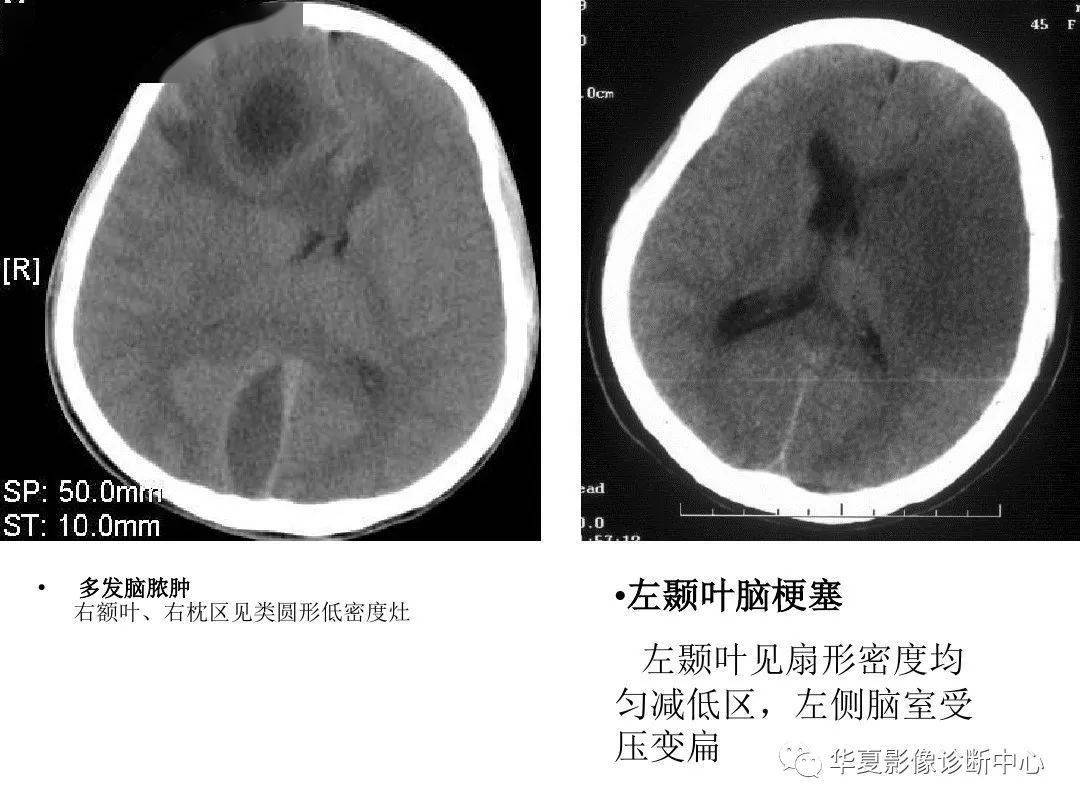

颅脑损伤及脑血管病ct判读与临床ppt